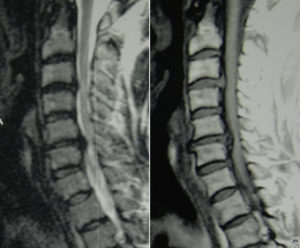

- МРТ;

Как правило, наиболее точно заключение МРТ, а все остальные процедуры назначаются только в случае особой необходимости.

Способ диагностики заболевания подбирается врачом-невропатологом исходя из общего состояния больного. В процессе консультации обязательно производиться внешний осмотр шейного сегмента позвоночника в состоянии покоя и при движении на наличие искривлений и деформаций. Для точного определения болезни и ее характера используются такие виды обследований:

- проведение компьютерной томографии, позволяющей выявить не только грыжу, но и иные повреждения костной или мышечной ткани. Ввиду двухмерности изображения, метод диагностики используется исключительно в тех случаях, когда пациенту нельзя провести обследование на аппарате МРТ;

- магнитно-резонансная томография. Благодаря применению радиоволн и магнитов, обеспечивает получение полного трехмерного изображения исследуемой зоны. Это позволяет оценить не только размеры грыжи и место ее возникновения, но и рассмотреть наличие защемления нервных окончаний;